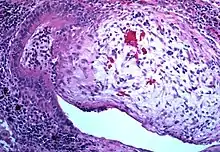

Lung biopsy

Transthoracic lung biopsies are preferable for diagnosis of constrictive BO compared to transbronchial biopsies; regardless of the type of biopsy, a diagnosis may only be achieved by examination of multiple samples.[30] Transthoracic biopsies are preferred over transbronchial due to the heterogeneity and distribution of the lesions.[11] OB can be further classified into two categories: constrictive or proliferative.[11] The constrictive pattern is demonstrated by peribronchiolar cellular infiltrates which eventually causes small airway damage and leads to subepithelial fibrosis.[11] The bronchial muscle can eventually become fibrosed which can be identified with trichrome staining.[11] In regards to proliferative disease, intraluminal buds called "Masson bodies" fill the lumen, which results in bronchiolar plugging.[11] Often people with proliferative disease will show butterfly wing-like appearance under microscopy.[11] One key determinate that can be seen on biopsy to differentiate constrictive from proliferative disease is the extent of lesions. Both lesions are localized from the small bronchi to the membranous bronchi, but in constrictive disease the lesions are intermittent while proliferative disease has a continuous distribution.[11]